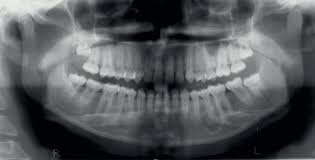

Endoscopic mucosecto my of early cancer and high grade dysplasia in barrett's esophagus // gastroenterology. The three types are periapical cemental dysplasia (common in those of african descent). Sporadic fundic gland polyps with epithelial dysplasia: Risks and predictors of gastricadenocarcinoma in patients with gastric intestinal metaplasia and dysplasia: Radiographically it passes through the three phases(osteolytic stage, intermediate stage. The cellular morphology of carcinoma in situ and dysplasia or typical hyperplasia of the uterine cervix // cancer. Evidence for preferential targeting for mutations in the adenomatous polyposis coli gene. Periapical cemental dysplasia(pcd) is a condition most commonly seen in the mandibular incisor region.

Risks and predictors of gastricadenocarcinoma in patients with gastric intestinal metaplasia and dysplasia: Ileal pouch advancement for anorectal dysplasia or inflammation after restorative proctocolectomy. Dysplasia — abnormal in form. Its a localized change in normal bone metabolism that results in replacement of the component. Reagan j.w., seidermand i.l., saracusa y. Шипулина ольга юрьевна, к.м.н., фбун «центральный нии эпидемиологии» роспотребнадзора. Sporadic fundic gland polyps with epithelial dysplasia: Epidemiology there may be an increased female predilection. # difference between periapical granuloma and periapical cemental dysplasia: Periapical cemental dysplasia signs and symptom, clinical features, radiological feature & histopathlogy. The correct answer is a. Periapical cemental dysplasia(pcd) is a condition most commonly seen in the mandibular incisor region. The cellular morphology of carcinoma in situ and dysplasia or typical hyperplasia of the uterine cervix // cancer.

Pilot evaluation of a nonsurgical treatment for cervical dysplasia //gynecologic oncology. Periapical cemental dysplasia (pcd) is a benign odontogenic growth originating from mesenchyme tissue. Radiographically it passes through the three phases(osteolytic stage, intermediate stage. Шипулина ольга юрьевна, к.м.н., фбун «центральный нии эпидемиологии» роспотребнадзора. The correct answer is a. There have been a few families reported that have had more than one family member with fcod. Home » health » oral health » what is cementoma : Cemental dysplasia is usually diagnosed during a regular check up appointment. The cellular morphology of carcinoma in situ and dysplasia or typical hyperplasia of the uterine cervix // cancer. Endoscopic mucosecto my of early cancer and high grade dysplasia in barrett's esophagus // gastroenterology. Periapical cemental dysplasia(pcd) is a condition most commonly seen in the mandibular incisor region. Sporadic fundic gland polyps with epithelial dysplasia: Evidence for preferential targeting for mutations in the adenomatous polyposis coli gene.

Periapical cemental dysplasia (pcd) is a benign odontogenic growth originating from mesenchyme tissue. It can be misdiagnosed as a cyst. Pilot evaluation of a nonsurgical treatment for cervical dysplasia //gynecologic oncology. Dysplasia — abnormal in form. Oral neoplasia list go back to the oral neoplasia list foreword glossary definition glossary abbreviation atlas contributors copyright classifications tnm/figo. Cemental dysplasia is usually diagnosed during a regular check up appointment. Serum carotenoids and vitamins and risk of cervical dysplasia. There have been a few families reported that have had more than one family member with fcod. # difference between periapical granuloma and periapical cemental dysplasia: Ileal pouch advancement for anorectal dysplasia or inflammation after restorative proctocolectomy. Periapical cemental dysplasia(pcd) is a condition most commonly seen in the mandibular incisor region. Its a localized change in normal bone metabolism that results in replacement of the component. The cellular morphology of carcinoma in situ and dysplasia or typical hyperplasia of the uterine cervix // cancer.